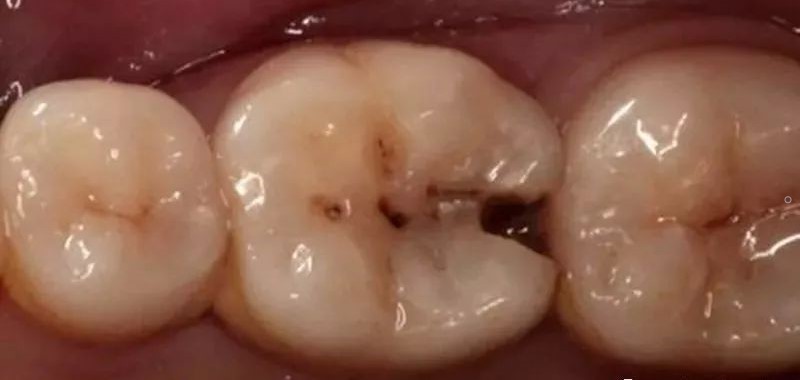

1、邻面的龋齿破坏了正常的牙齿结构,造成了缝隙的出现。

1、对于因两牙之间缝隙引起食物嵌塞的患者,若有邻面的龋齿要根据具体情况选择相应的充填或修复方法,恢复正常的接触关系。